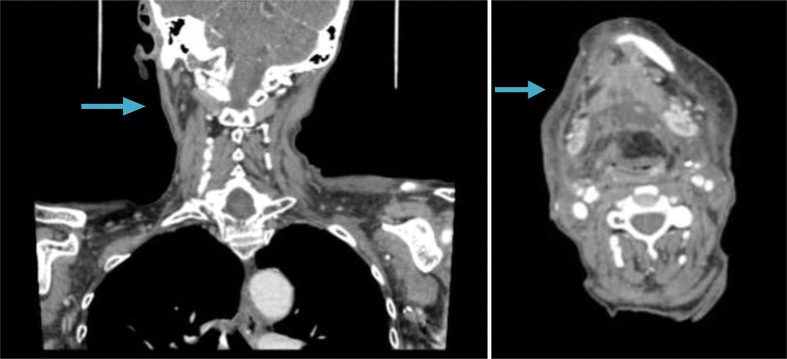

A computed tomography scan of the neck was performed on postoperative day 23, as the patient had developed a further small collection in the neck. The scan showed several small collections of fluid bilaterally (Fig 2). As the patient remained asymptomatic, these were not treated operatively and underwent observation. By postoperative day 28, the discharge had completely dried up and the patient made an uneventful recovery.

Figure 2.

Computed tomography of the neck on postoperative day 23